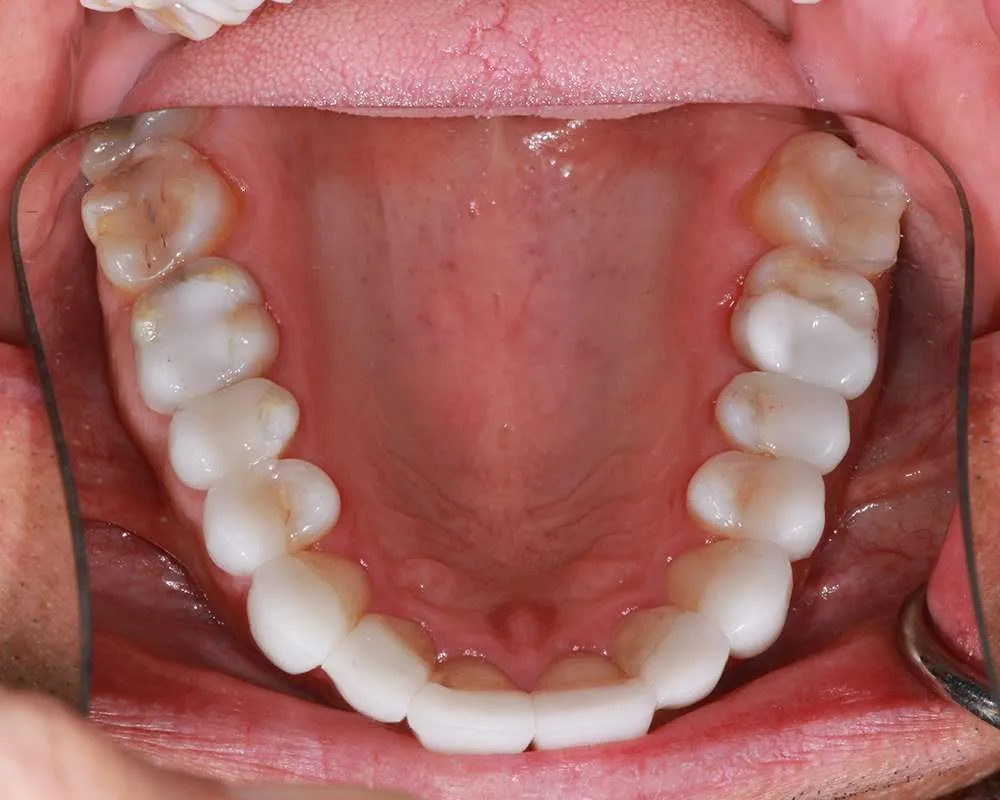

Complex Cases

Witness the Remarkable Changes We Can Achieve